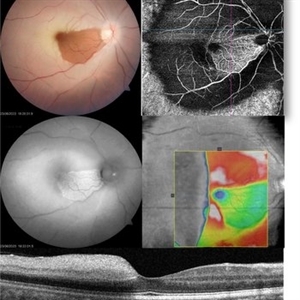

Spent-force

Composite OCT image of left eye of a 53 years old male diabetic patient with recuuent spongy diabetic macular edema. Structural image depicts presence of ozurdex temporal to fovea. B-Scan image shows localized action of ozurdex in retinal tissue underlying it while cystoid changes are seen nasal to foveal center

Photographer: Maneesh Bapaye MD

Condition/keywords: diabetic macular edema, Ozurdex implant